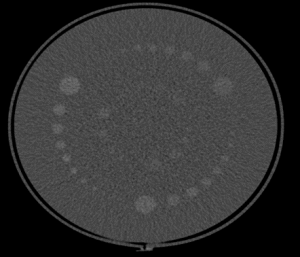

| ماژول اندازه گیری یکنواختی تصویر:

| ابعاد و ساختار | ظرف استوانه ای به قطر 198 میلیمتر و پهنای 34 میلیمتر دارای دو دریچه برای پر یا خالی کردن آب مقطر

| پارامترها قابل بررسی | یکنواختی تصویر و آرتیفکتها

| محدوده اندازه گیری | اعداد سی تی

| جنس | ظرف استوانه ای اکریلیک حاوی ماده یکنواخت ( آب مقطر یا هوا) | |